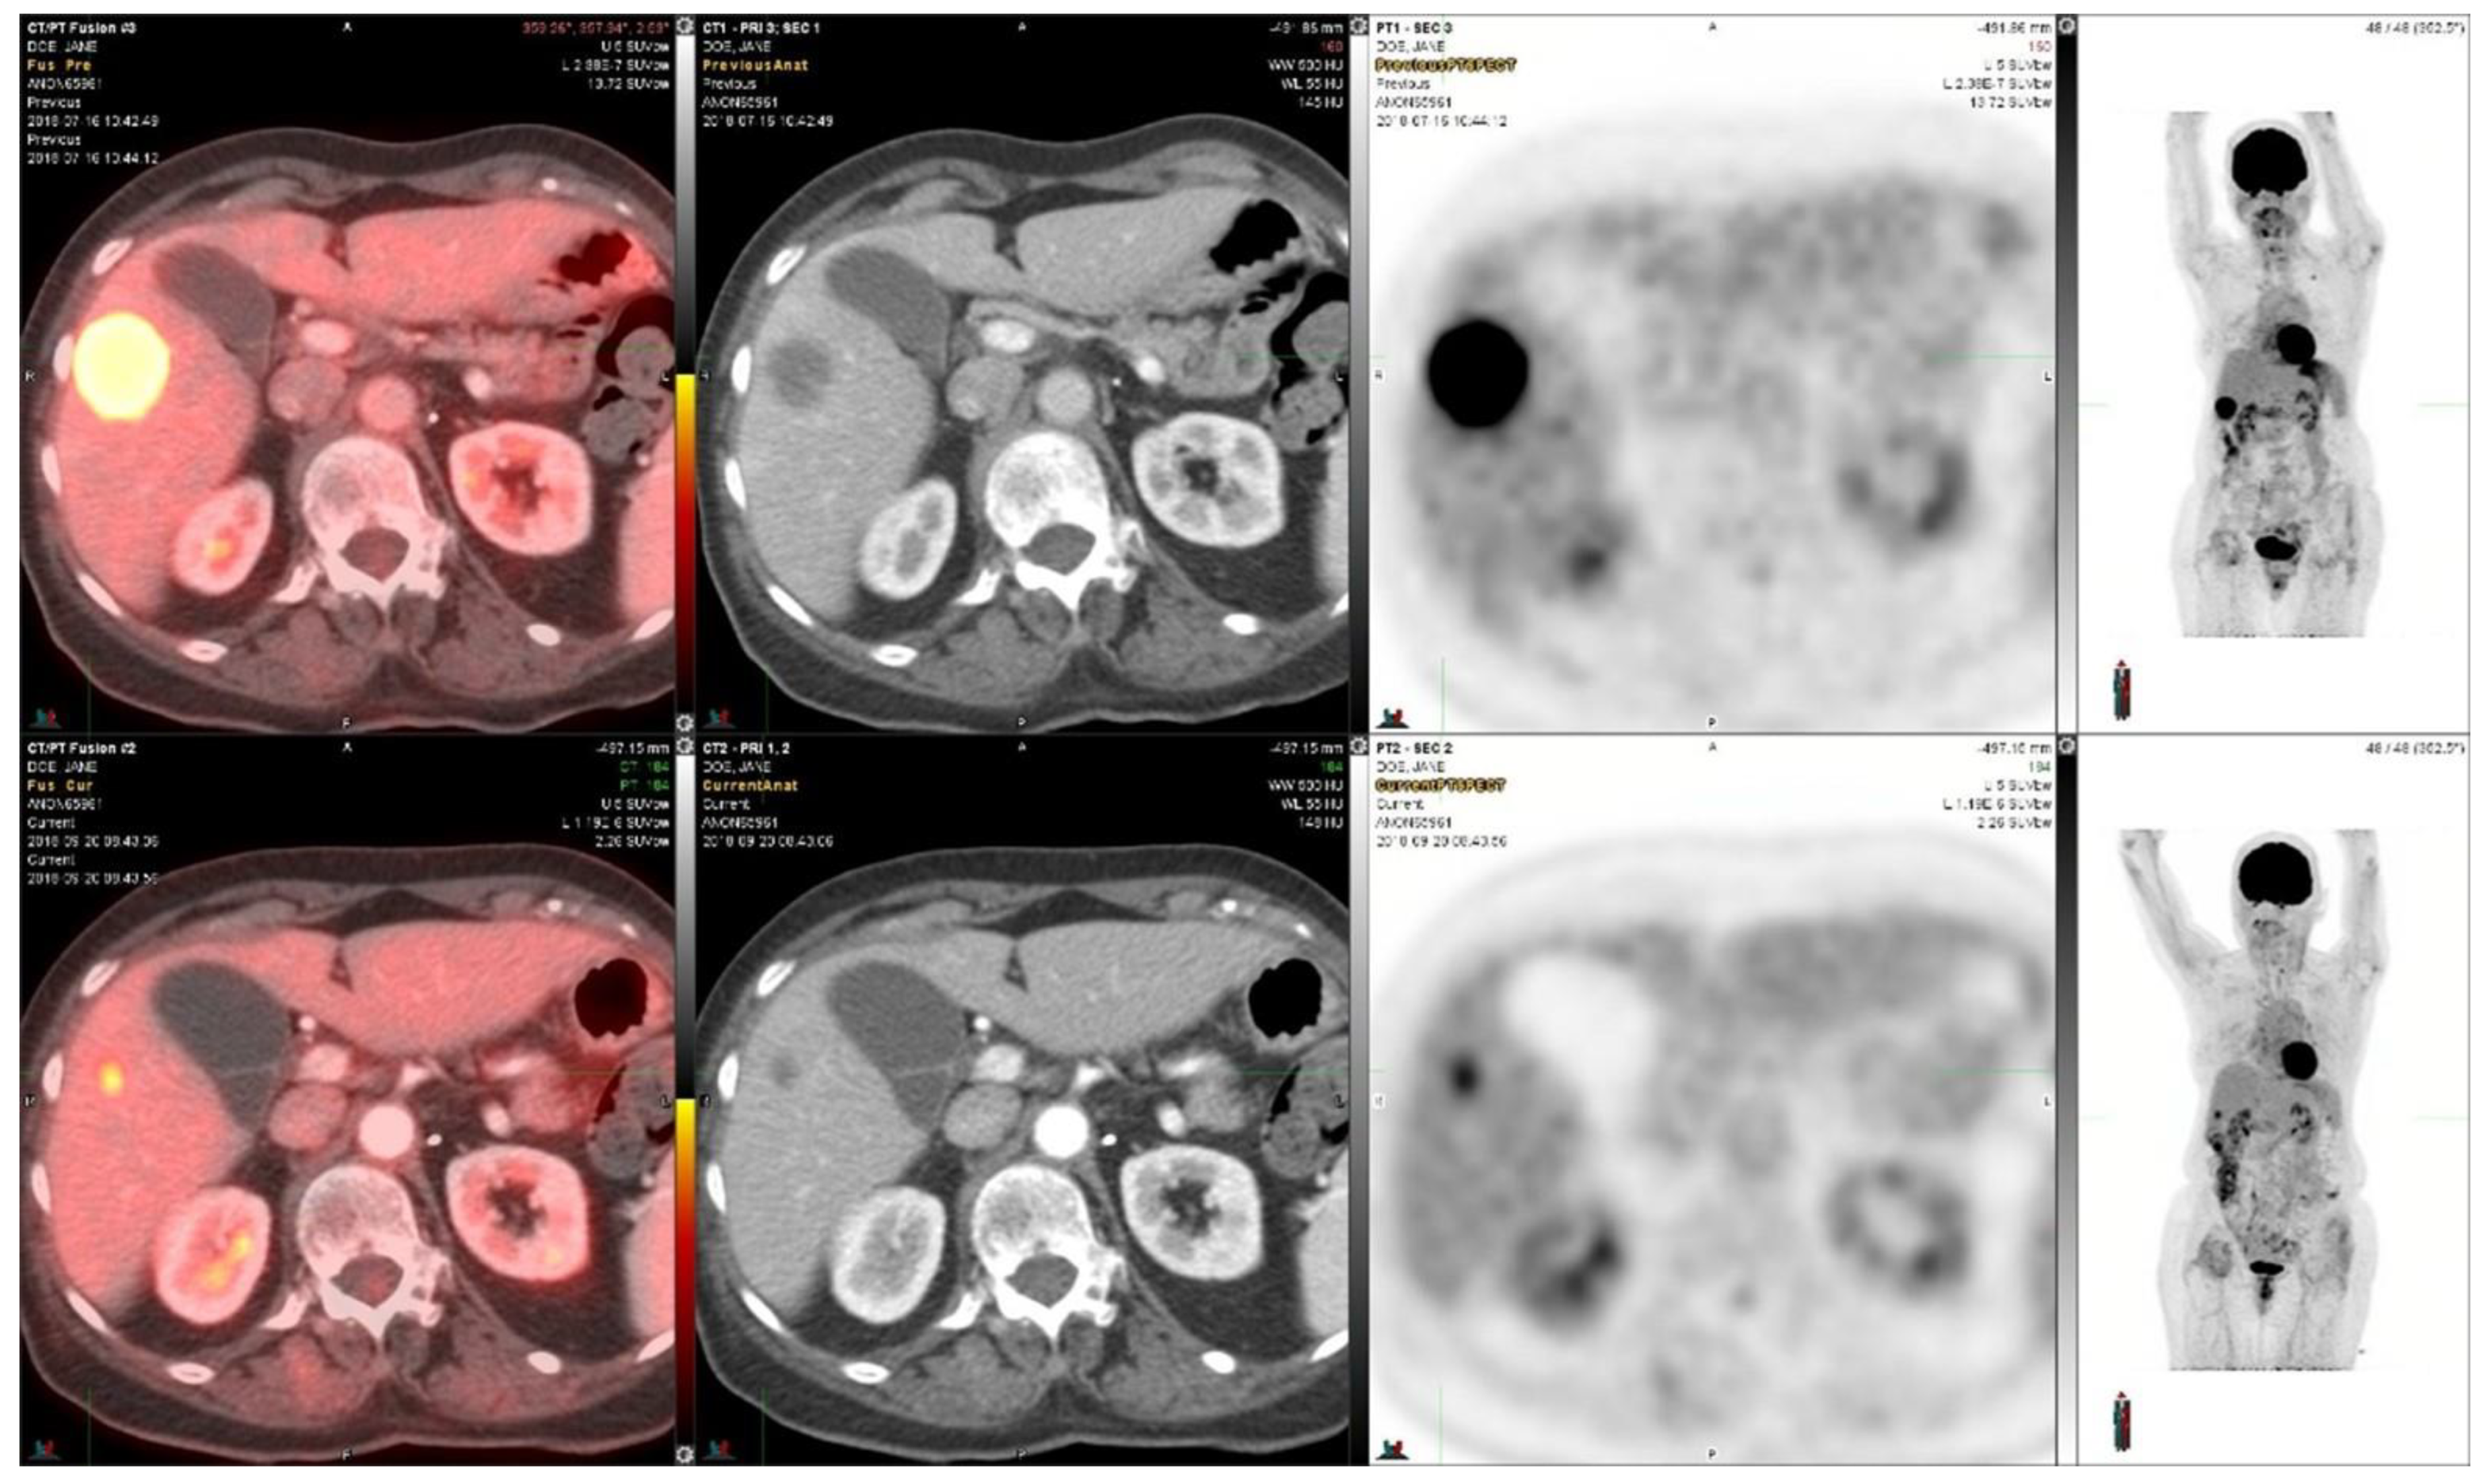

Case 2: A female in her 70s was diagnosed with stage IV metastatic adenocarcinoma of the lung five years earlier. The initial treatment consisted of weekly paclitaxel in combination with carboplatin for two months and mediastinal external beam radiation therapy. Genomic testing revealed an RET fusion-positive lung cancer. Based on this, the patient was started oral vandetinib, a multi-kinase VEGF inhibitor with RET activity, and everolimus, an mTOR inhibitor, which were to be taken daily for twelve cycles and thereafter every other day based on a clinical trial [15]. Following progression of the disease, the patient was started on selpercanitib (an RET inhibitor). The initial PET/CT scan showed activity in the liver. A subsequent scan at re-staging after two cycles showed a response in the liver metastasis (Figure 2). The SUVmax decreased from 21.0 to 5.2, i.e., −75%, in the liver metastasis shown in Figure 2. The liver tumor size decreased from 3.1 cm × 2.8 cm to 0.9 cm × 0.8 cm. She received a total of 12 cycles and progressed on therapy. The overall survival of stage IV metastatic lung adenocarcinoma is more than five years.

Figure 2. 18F-FDG-PET/CT images in a patient with metastatic adenocarcinoma of the lung which had an RET-mutation and was treated with selpercanitib for 12 cycles. The upper panel demonstrates the situation before selpercanitib treatment; from the left, transaxial PET/CT fusion images, CT images, and PET images at the level of the largest liver metastasis and the furthest right image shows n MIP image from the whole-body PET study. The lower panel shows the situation after two cycles of selpercanitib two months later using images at the same level in the transaxial images and in the MIP image shown furthest to the right. In this liver metastasis, the SUVmax decreased from 21.0 to 5.2, corresponding to a 75% decrease.